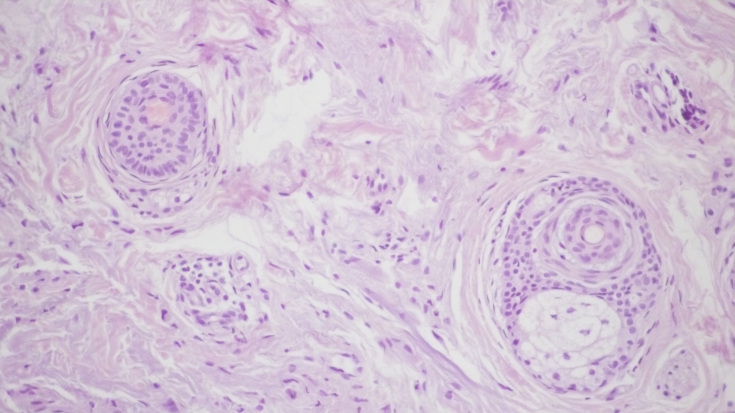

При контрольній гістологічній підготовці ділянки шкіри перед проведенням лікувальних заходів відзначалася вогнищева значно виражена запальна інфільтрація в дермі у вигляді вогнищевих скупчень лімфоцитів і гістіоцитів. (мал. 1а, b). Проліферація дрібних судин капілярного і синусоїдного типу супроводжувалася периваскулярною лімфоїдно-клітинною інфільтрацією (мал. 1c). Навколо окремих волосяних фолікулів і сальних залоз запальна інфільтрація стимулювала проліферацію фібробластів і розвиток склеротичних процесів. (мал. 1d).

Мал. 1. Морфологічна картина шкіри перед лікувальними заходами: вогнищева запальна інфільтрація дерми, х200; запальна інфільтрація навколо волосяних фолікулів, ознаки фіброзу, х200; проліферація дрібних судин капілярного типу з периваскулярної лімфоїдно-клітинною інфільтрацією, х200; сальні залози з вогнищевою запальною інфільтрацією в прилягаючій дермі, х200.

Мал. 3. Морфологічна картина шкіри перед проведенням лікувальних заходів: виражена вогнищева запальна інфільтрація дерми, х200; запальна інфільтрація навколо волосяних фолікулів, ознаки фіброзу, х200; проліферація дрібних судин капілярного типу з периваскулярної лімфоїдно-клітинною інфільтрацією, х200;